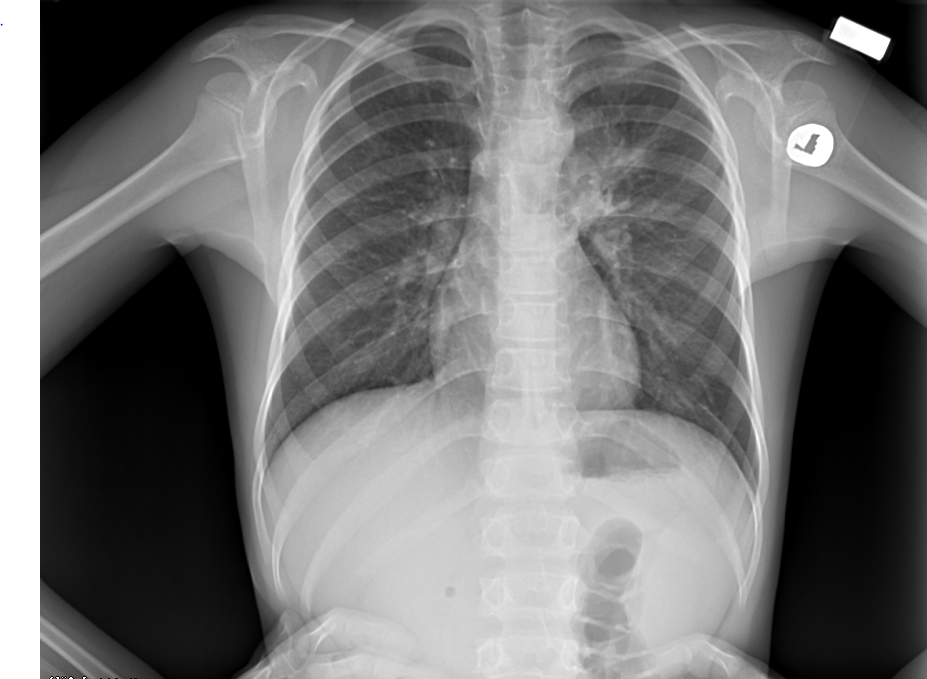

Рентгеновские снимки при пневмоцистной пневмонии